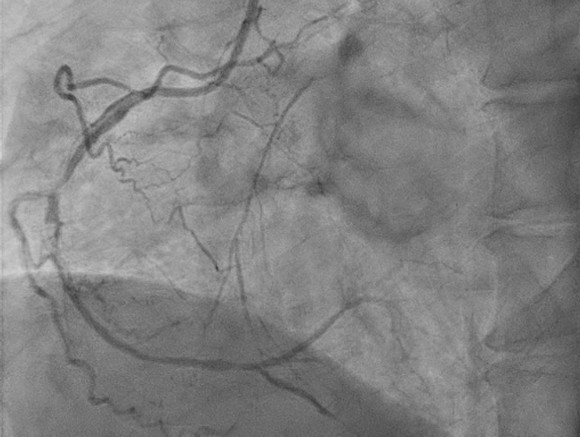

Coronary angiogram was performed 4 months ago(2025/06/12), which showed 3-vessel disease and middle left circumflex (LCx) chronic total occlusion (CTO). He was then referred to CVS OPD for SDM of CABG. After discussion, the patient declined CABG due to personal factors (single/ poor economic condition/ pre-dialysis status) and decided PCI. PCI was postponed scheduled for several times due to his work schedule before this admission.